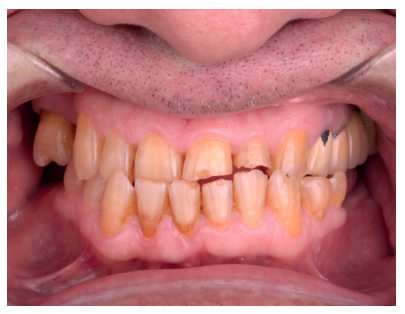

Se presenta el siguiente caso clínico de un varón de 64 años, que en un primer momento no presenta ningún antecedente, ni personal ni familiar, de interés, no toma ninguna medicación ni presenta hábito tabáquico. Acude a la Universidad Complutense de Madrid diciendo textualmente: “necesito ponerme dientes”. Se trata de un paciente con complejo para sonreír y que busca una solución funcional y a la vez estética (Figura 1).

En una primera visita se realiza la historia clínica, serie de fotos intraorales y extraorales, así como una radiografía panorámica para planificar el caso conjuntamente entre el Máster de Prótesis Bucofacial y el Máster de Cirugía Bucal e Implantología. (Figura 2). Como consecuencia de las ausencias del primer y segundo molar inferior de ambos cuadrantes, el paciente presentaba desgastes generalizados en el resto de los dientes debido una sobrecarga e inestabilidad oclusal. Con todos los registros clínicos y radiográficos, se decidió conjuntamente entre Cirugía y Prótesis realizar una rehabilitación completa superior e inferior sobre dientes e implantes. Debido a las limitaciones económicas del paciente, se sugirió la posibilidad de emplear los segundos molares inferiores, que se encontraban retenidos, como material de injerto para la posterior colocación de implantes en esas áreas. Tanto el tercer como el cuarto cuadrante fueron tratados de la misma forma.